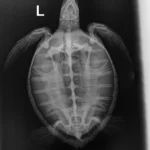

2.50 kg/5.00 lbs juvenile Atlantic Green sea turtle

Plastron (belly): Urchin spines and some small abrasions

External Wounds: Hook in left shoulder

Head/Flippers/Soft Tissue: Notch missing out of trailing edge of the right flipper